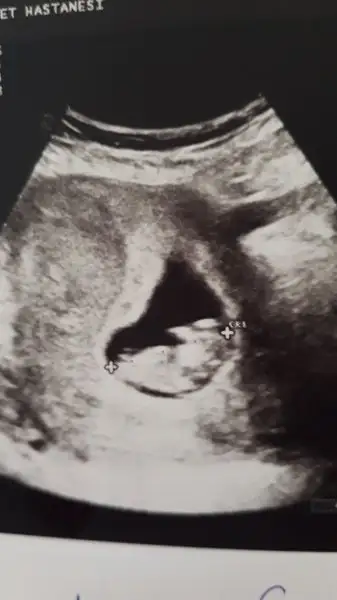

Bana da yorum yaparmısınz

Milana firuze Milana firuze yaz demistin canim. Gittigim ilk kontrolde bagdas kurdu gostermedi. 14 +5ti doktor cok ugrasti ama acmadi. Dun 17+1de gittik. Yine bağdaş kurmuştu. Ama birazcik acti doktor yuksek ihtimal erkek dedi

Bana yazdığın için cok sağol ven demişdim erkek diye, sağlıkla kucağna alırsın inşallah oğlunu.